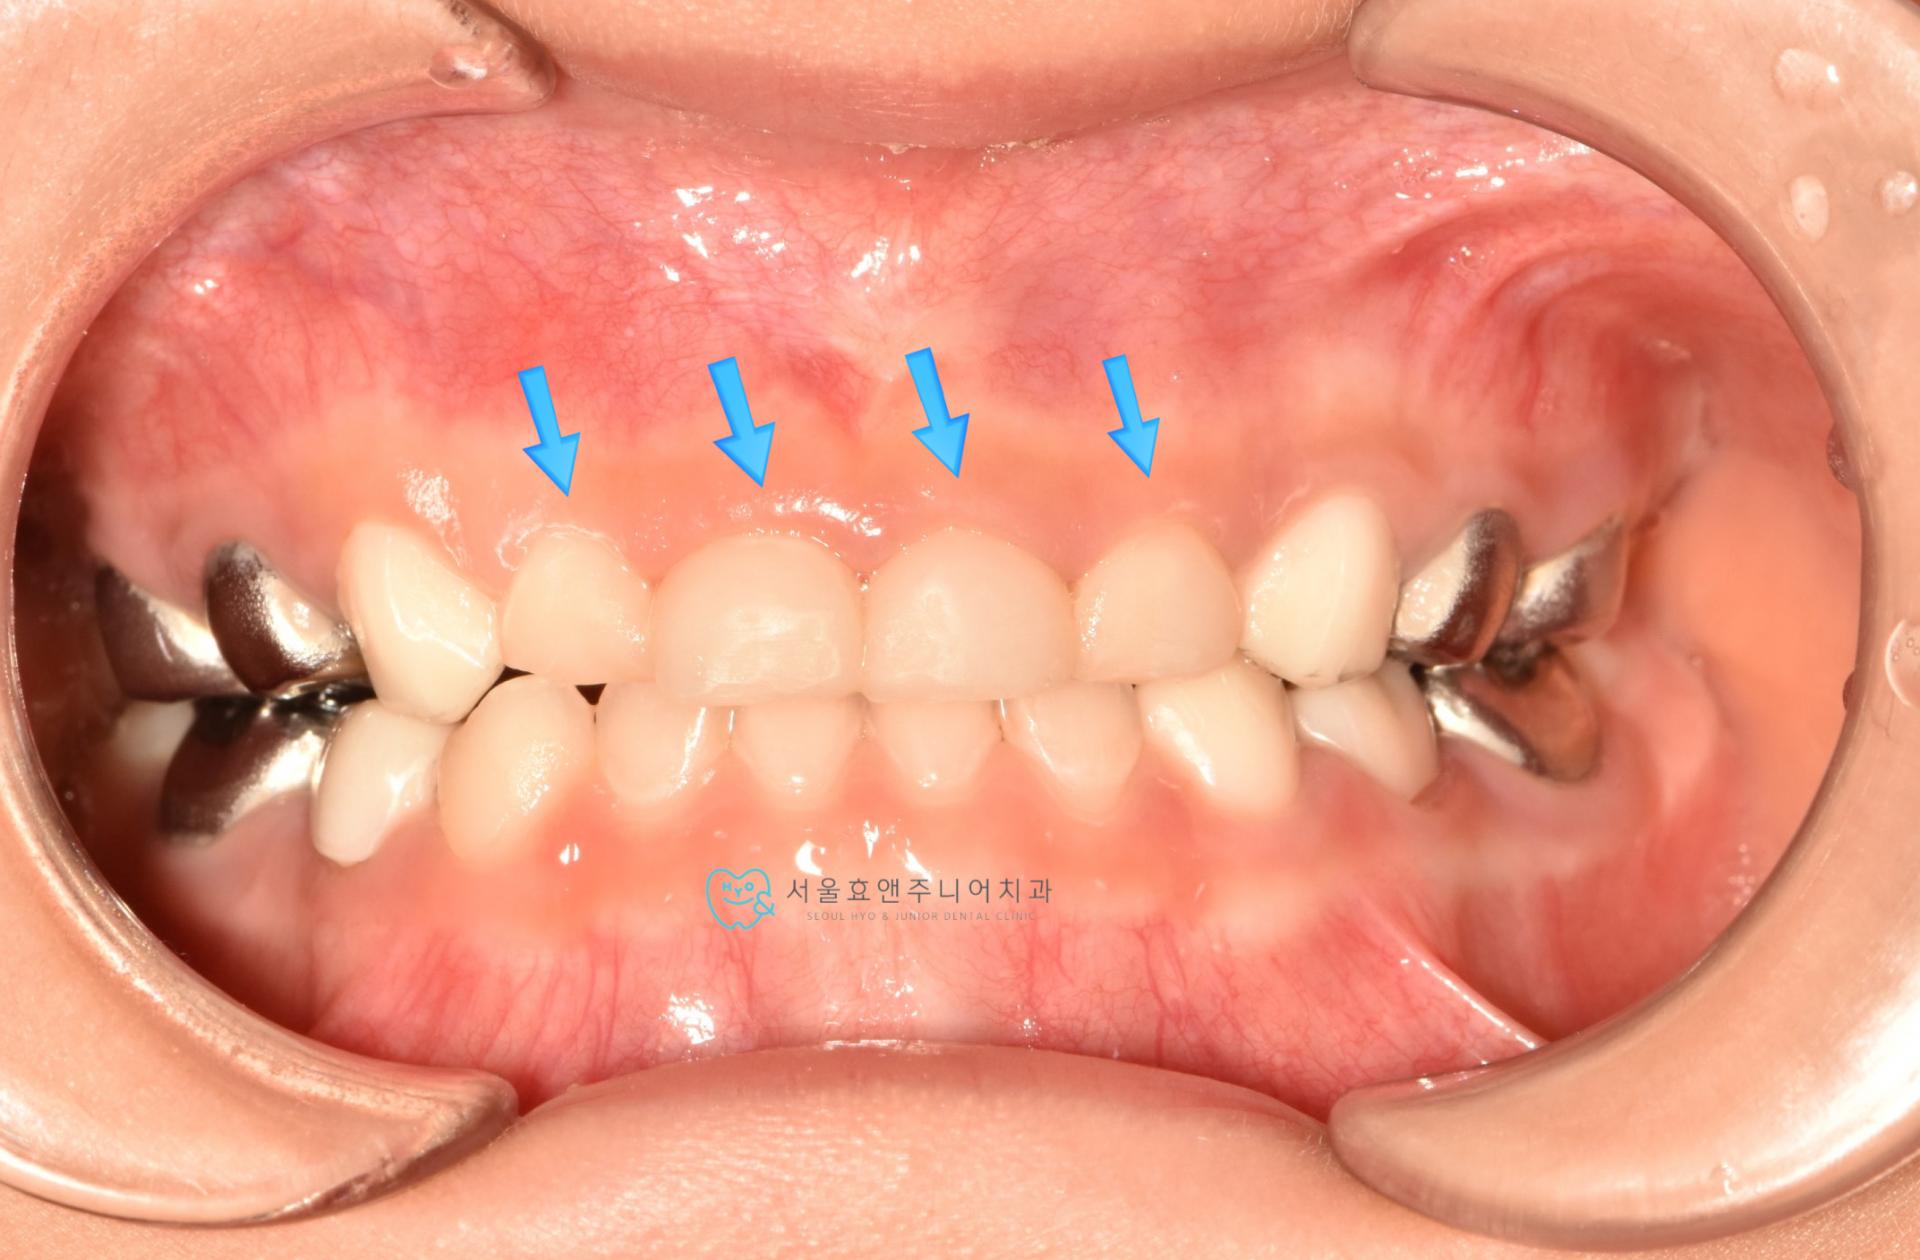

치료후 사진입니다.(치료후 3개월)

충치를 레진으로 치료한 뒤입니다. 치아의 양 벽면을 레진으로 깨끗하게 수복하였습니다.

수면치료 하에 앞니 4개를 모두 레진치료하였습니다. 충치의 범위가 넓어 레진치료하기가 까다로웠지만, 결과는 예쁘게 되었네요. 치아가 깨끗하고 예뻐져서 부모님도 아이도 만족하는 치료였으며 저도 보람을 느꼈습니다. 아직 첫번째 앞니는 2년정도 , 두번째 앞니는 3년 넘게 더 쓸것으로 보입니다.